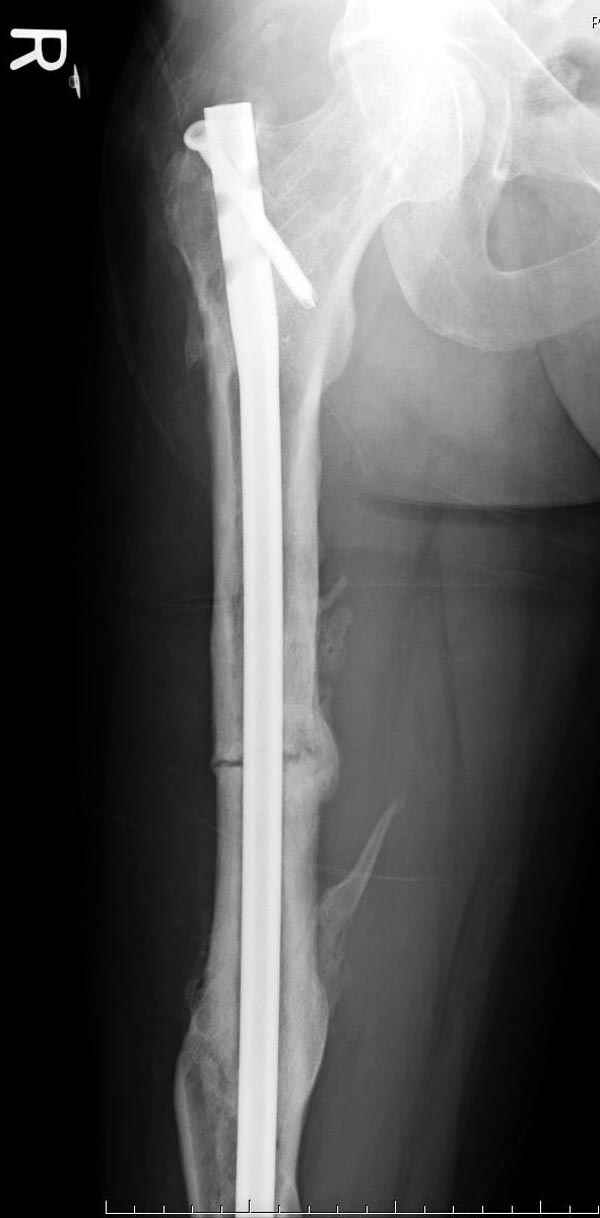

На следующий день произвели интрамедуллярный остеосинтез: этапы во время операции (рис №8, №9)

и последующих снимках (рис №10, 11, 12, 13) перелом сростается и передвигается с полной нагрузкой.

При обзоре причин перелома, на снимке №2 обнаружили, что один из стержней аппарата наружной фиксации проходил только через передний кортекальный слой, что создало стрессовую зону на бедре и в результате перелом из-за незначительной травмы.